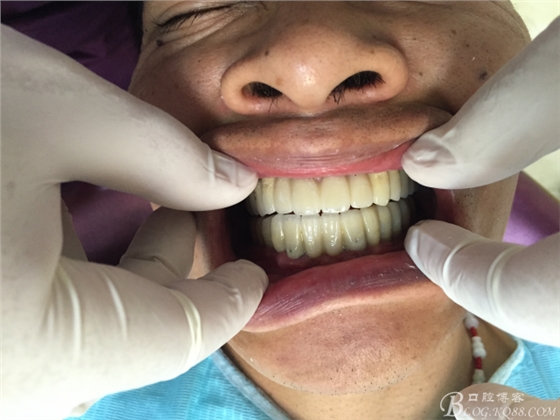

患者37歲 男 全口牙周病 手術(shù)一次完成 全程3小時全口種植修復(fù)全口種植修復(fù)全口種植修復(fù)全口種植修復(fù)全口種植修復(fù)全口種植修復(fù)全口種植修復(fù)全口種植修復(fù)全口種植修復(fù)全口種植修復(fù)全口種植修復(fù)全口種植修復(fù)全口種植修復(fù)全口種植修復(fù)全口種植修復(fù)